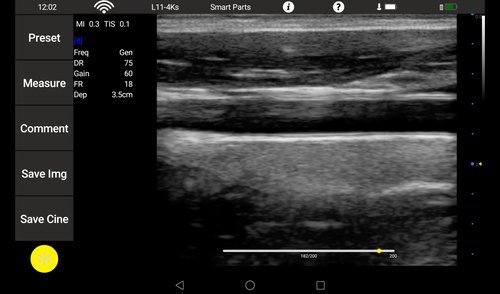

Linearsonde (L11-4Ks) 7,5 MHz 6-11 MHz L40 Gefäße, Small Parts, Anästhesie, Orthopädie